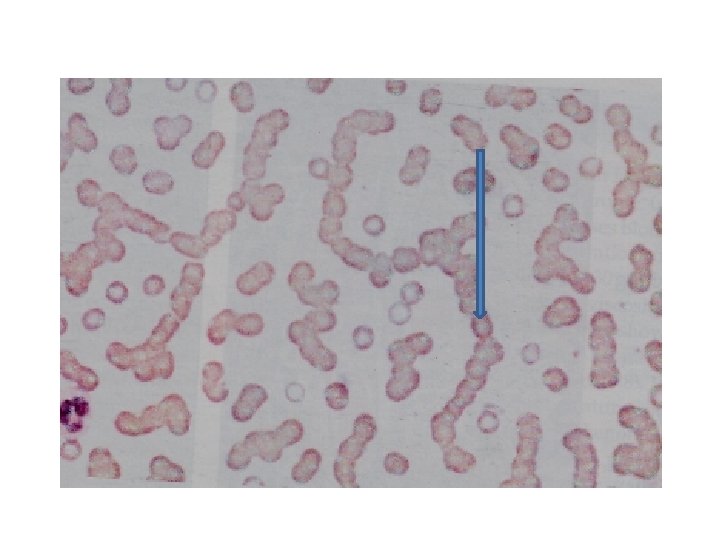

LABORATORY FEATURES • Increased Plasma cells (Abnormal Plasma cells) in the bone marrow (more than 30%) • Anemia • Neutropenia • Thrombocytopenia • Rouleaux formation • Very high ESR • High calcium